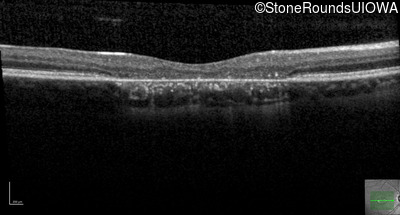

This 22 year old man had macular abnormalities noted incidentally at a routine eye exam at age 19. Since then, he has experienced a gradual loss of acuity particularly in the left eye.